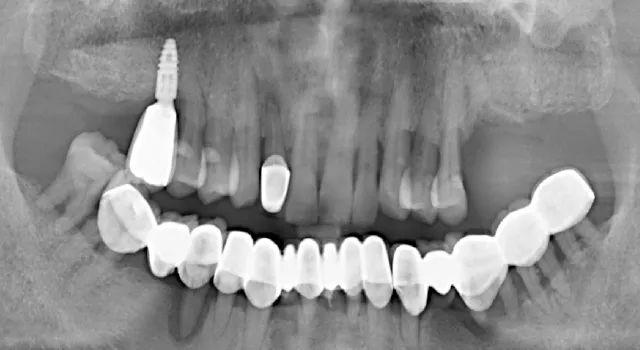

無獨(dú)有偶,一起看看那些價(jià)格便宜但醫(yī)療質(zhì)量不過關(guān)的種植牙:劣質(zhì)種植體導(dǎo)致的種植牙失敗

手術(shù)失敗的種植牙,使用壽命僅僅只有2個(gè)月(種植窩空虛,頰側(cè)嵴頂骨缺損)